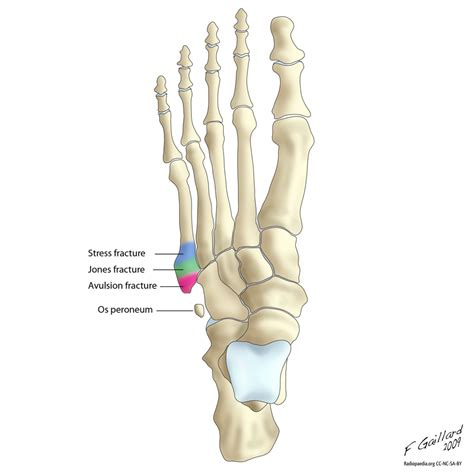

Diagnosing a Fifth Metatarsal Fracture

Diagnosing a Fifth Metatarsal Fracture typically involves a combination of physical examination and imaging tests. The diagnostic process may include:

• Physical Examination: A healthcare provider will examine the foot, checking for swelling, tenderness, and deformity.

• X-Rays: X-rays are the primary imaging tool used to confirm the presence and location of the fracture.

• CT Scans or MRIs: In some cases, more detailed imaging such as CT scans or MRIs may be required to assess the extent of the fracture and plan treatment.